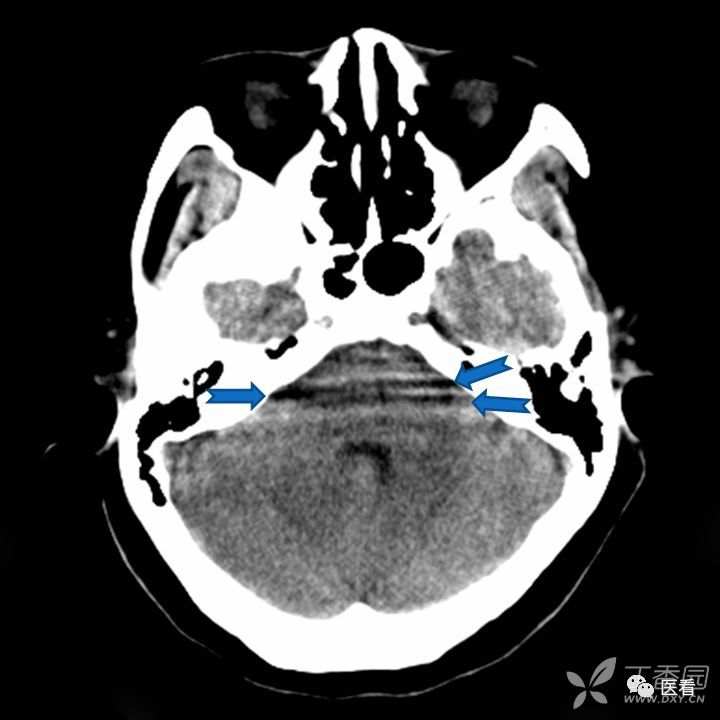

亨氏暗区

颅底(致密)骨产生的横行或放射状伪影,与设备性能也有关系

下图为16拍MSCT,伪影较轻。

此图为双排螺旋 CT图像, 伪影较16层及以上MSCT显著的多。